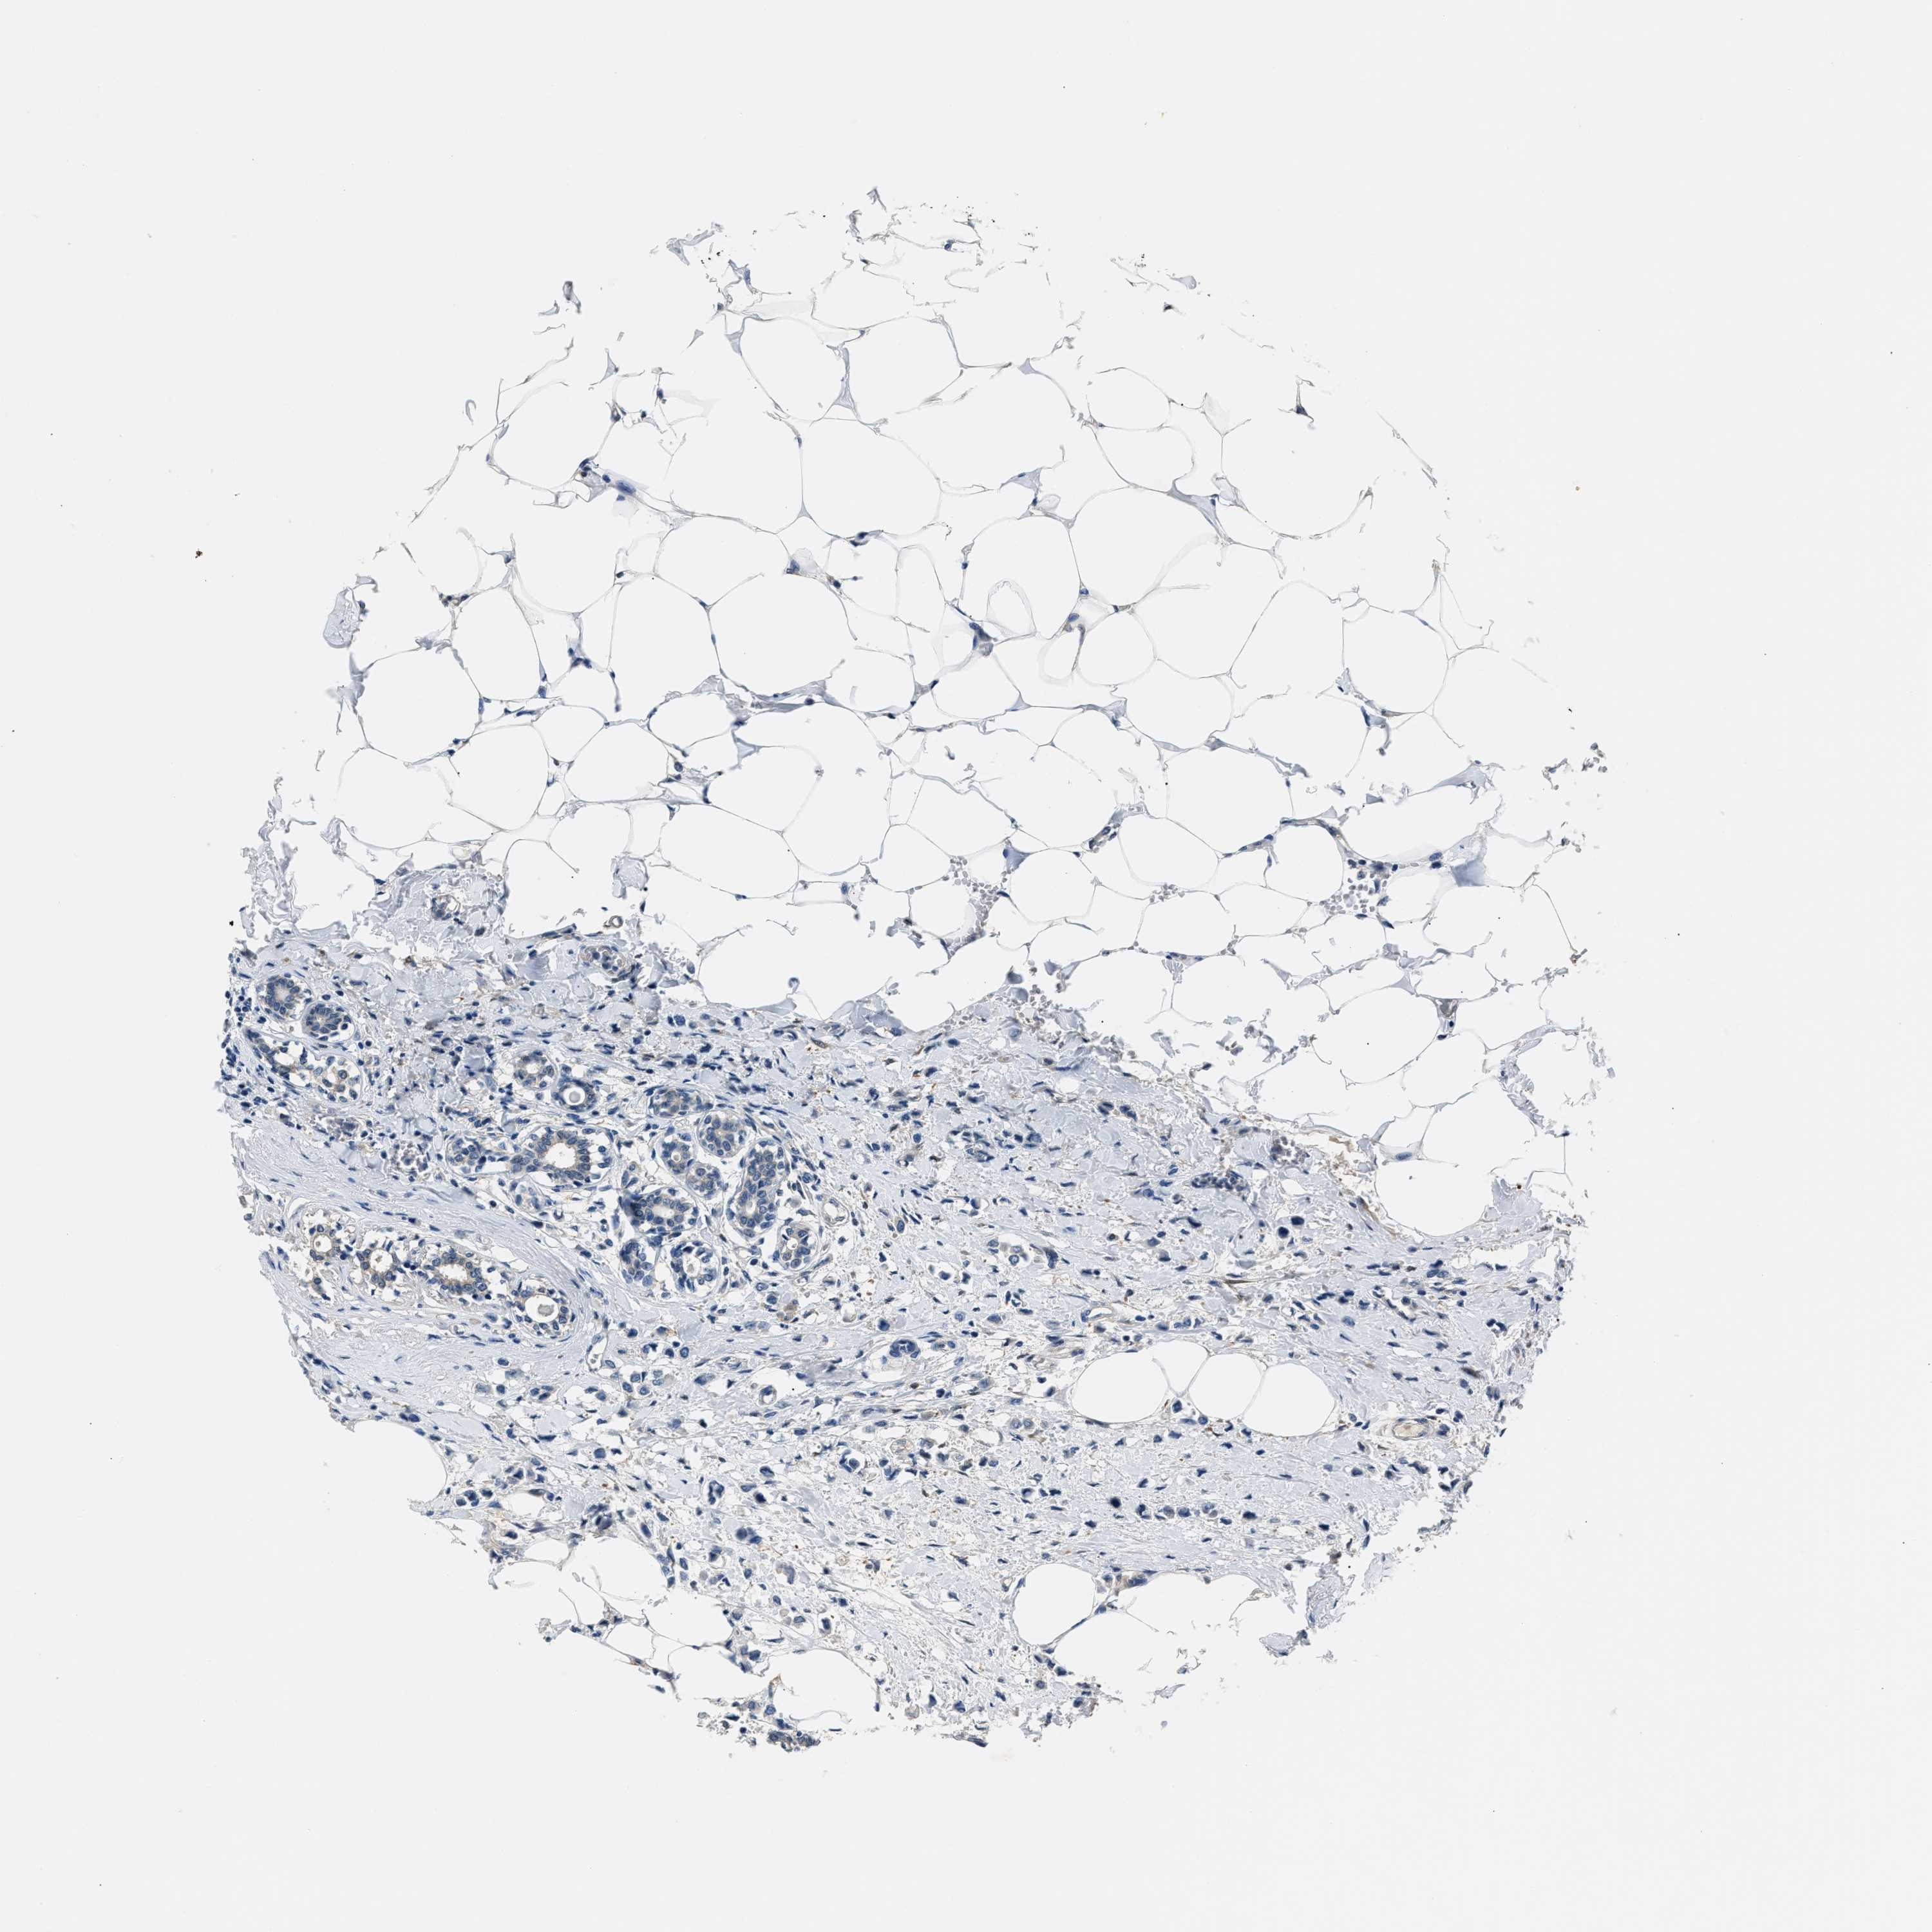

CANCER BREAST CANCER Show tissue menu

BRCA TCGA BRCA VALIDATION PROTEIN EXPRESSION

ANTIBODIES

AND

VALIDATION